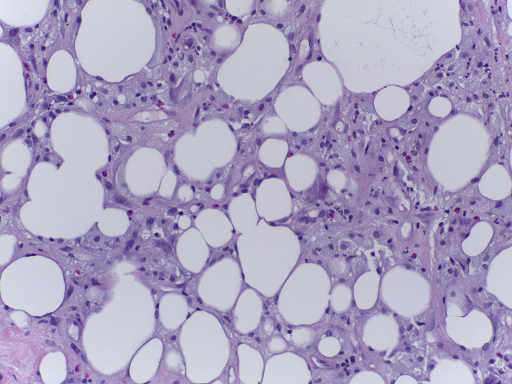

The microscopy dataset is composed of 400 training and 100 test images, with the four classes equally represented (see Fig. 2). All images were acquired in 2014, 2015 and 2017 using a Leica DM 2000 LED microscope and a Leica ICC50 HD camera and all patients are from the Porto and Castelo Branco regions (Portugal). Cases are from Ipatimup Diagnostics and come from three different hospitals (Hospital CUF Porto, Centro Hospitalar do Tâmega e Sousa and Centro Hospitalar Cova da Beira). The annotation was performed by two medical experts. Images where there was disagreement between the Normal and Benign classes were discarded. The remaining doubtful cases were confirmed via imunohistochemical analysis. The provided images are on RGB .tiff format and have a size of 2048×1536204815362048\times 1536 pixels and a pixel scale of 0.42 μ𝜇\mum ×\times 0.42 μ𝜇\mum. The labels of the images were provided in .csv format. Participants were provided with a partial patient-wise distribution of the images of the training set. The test data was collected from a completely different set of patients, ensuring a fairer evaluation of the methods. Note that the training set is an extension of the one used for developing the approach in [3].

Refer to caption

(a) Normal

(b) Benign

(c) In situ

(d) Invasive

Fig. 2: Examples of microscopy images from the BACH dataset.